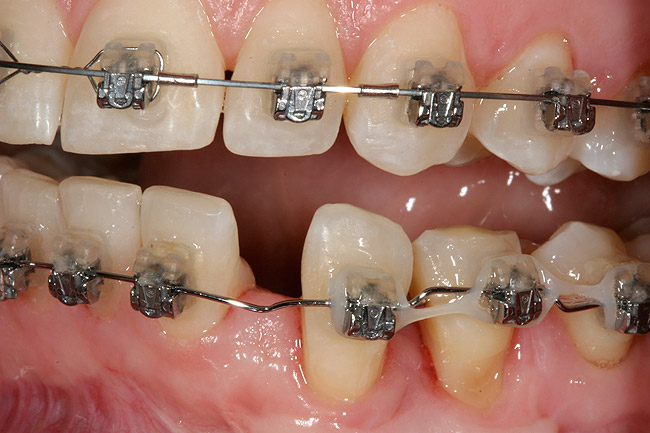

Figure 9: Orthodontic distraction osteogenesis to develop the implant site of tooth No. 23.

Figure 9

This treatment plan was elected with the premise to reevaluate treatment options during orthodontic tooth movement. Soft-tissue augmentation was initiated to correct the mucogingival defect in the area of teeth Nos. 21 and 22. A free gingival graft was performed to achieve an adequate band of attached and keratinized gingiva to resist potential stripping on the root surfaces of teeth Nos. 22 and 21 during orthodontic movement (Figure 8). Orthodontic movement then was initiated to site-develop position No. 23 for an implant (Figure 9 through Figure 11). Orthodontics also was used to idealize the patient’s occlusion and develop canine guidance to minimize occlusal load and maximize the redistribution of forces36-40 for protecting the future implant from deleterious forces. The space was opened around the peg lateral tooth No. 7, and the gingival levels were aligned for maxillary incisors. Bonding was performed to restore the length of teeth Nos. 8 through 10 and to bond the peg lateral to a normal tooth form, which allows the orthodontist to idealize the posterior occlusal scene and maintain canine guidance (Figure 12 and Figure 13).